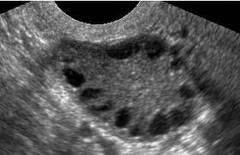

Õppematerjal "Hüperandrogeneemia" on koostatud sünnitusabi ja günekoloogia eriala spetsialistele, doktorantidele ja residentidele. Õppematerjal koosneb ühe haigusjuhu analüüsist ja teoreetilisest osast, kus antakse ülevaade steroidhormoonide ainevahetusest, rõhuasetusega androgeenidele, hüperandrogeneemia patogeneesist, kliinilistest sümptoomidest, diagnoosimisest ja ravist.